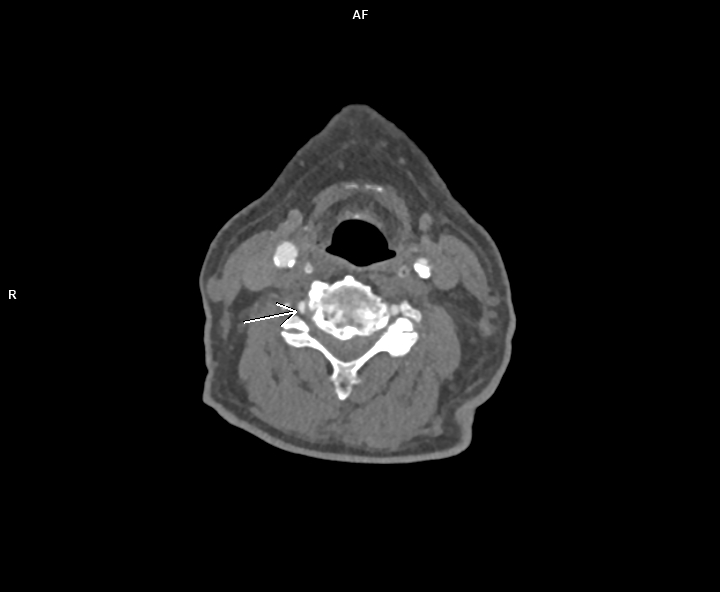

Figura 1: reconstrucție axială din achiziție angioCT trunchiuri supraaortice

Discuţie caz nr 116: Pe imaginile prezentate se observă reducere de calibru de 60-70% a arterei vertebrale drepte datorată compresiei extrinseci de către o hernie de disc extraforaminală. Leziunile severe de artere vertebrale, mai ales la pacienții tineri care nu au dezvoltat colaterale, produc leziuni cerebrale de fosă posterioare și / sau ganglioni bazali. La acești pacienți se recomandă angioCT sau, unde este posibil și există expertiză, angioRM de trunchiuri supraaortice pentru suspiciune de disecție de perete vascular.